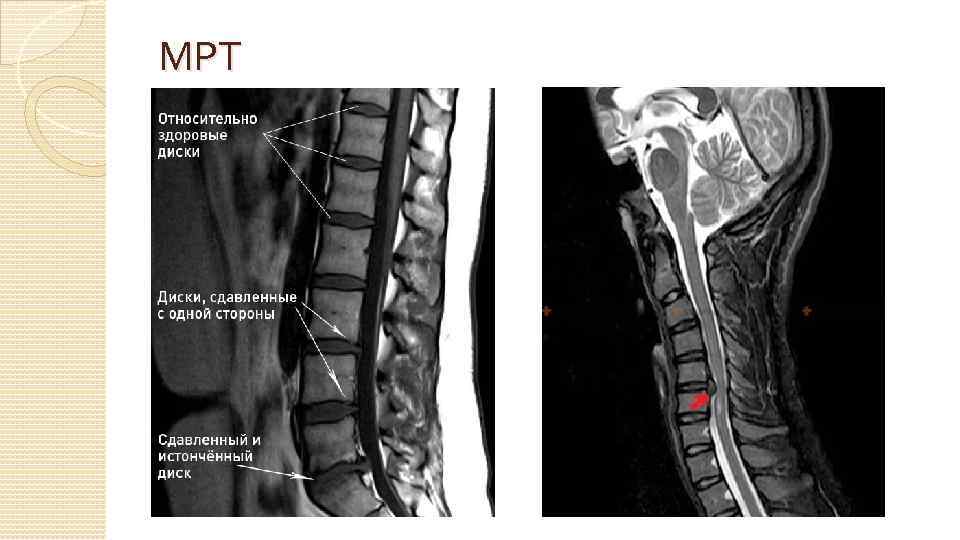

Методы диагностики Сбор анамнеза, жалоб Неврологическое обследование Рентгенография КТ МРТ Электронейромиография (ЭНМГ) ЭКГ, УЗИ БЦА, УЗИ органов брюшной полости и малого таза, ФГДС и др.

МРТ